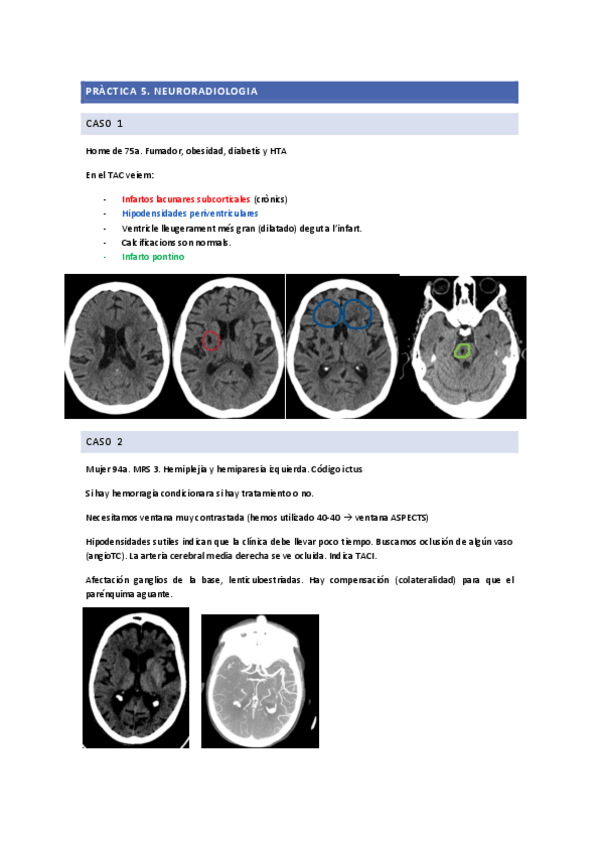

PRACTICA-5CASOS-NEURORADIOLOGIA.pdf